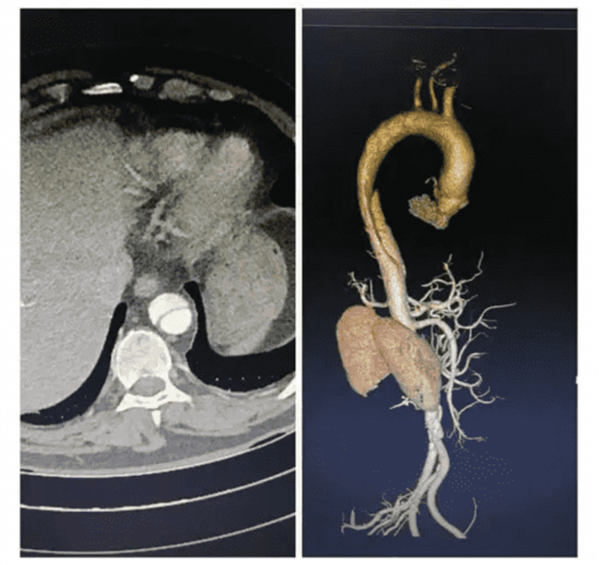

达摩院团队基于在“平扫CT+AI”方向上的技术积累,用三年多时间研发出AI模型iAorta,可在几秒内勾画主动脉及其血管腔,判断血管壁有无结构变化,从而精准识别AAS,将初诊漏诊率从48.8%降至4.8%。

其中,一名43岁患者因“上腹部钝痛12小时”入院,医生初诊考虑胆囊结石并开具上腹部平扫CT检查,iAorta模型从中发现主动脉夹层,患者随后接受主动脉CTA确诊,全程只用了1.6小时。